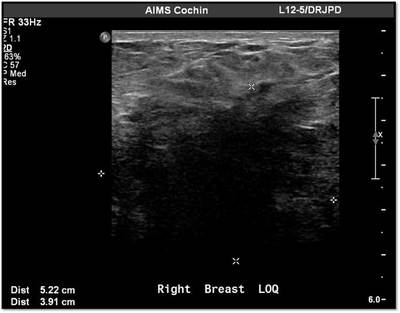

MG: Right breast shows focal asymmetric density in lateral quadrant extending for an area of 12.4 x 6.5 cm with no associated discrete mass or suspicious calcifications. Correlative ultrasound showed a heterogeneous area with echogenic vascular surrounding parenchyma in lateral quadrant with no discrete solid masses. MRI breast was performed on day 14 of LMP. Right breast shows an area predominantly consisting of fat in lateral quadrant extending for an area of 1.2×5.5x 8.9 cm along its maximum AP, ML and CC dimensions. This area is bright on fat suppressed T2 sequences and shows significant restriction on diffusion weighted sequences. There is rapid and progressive non mass enhancement in the above area extending anteriorly in to the nipple and posteriorly into the pectoralis major muscle. Two large and tortuous feeding vessels are seen to arise from the subclavian and axillary arteries respectively. Right breast shows predominantly fat containing mass showing abnormal enhancement described. The possibilities include vascular neoplasm or remotely fat necrosis. Ultrasound guided core biopsy was Suggestive of an inflammatory lesion, possibly fat necrosis. However enlarged and tortuous feeding arteries to the vascular mass was worrisome and we recommended an excision biopsy correlation. Excision biopsy showed “Multiple patchy areas of dense inflammatory infiltration in a background of fat necrosis”.